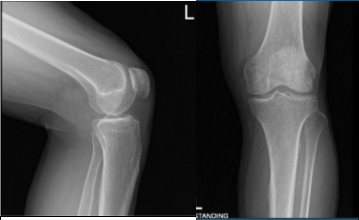

X Ray reports were presented and there are no significant degenerative changes. The patient wished to proceed with the injection to reduce pain and swelling. After a sterile prep, 7cc of 1% lidocaine and 80 ml of depo-Medrol were injected into the left knee jt.

AP and Latera View